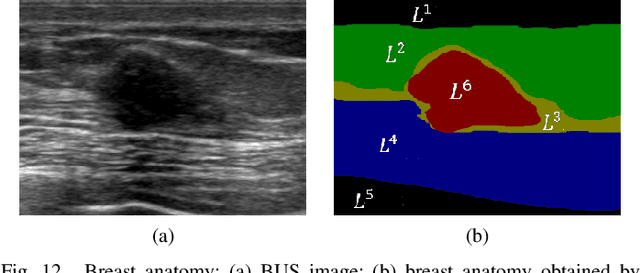

Abstract:Breast cancer is one of the most serious disease affecting women's health. Due to low cost, portable, no radiation, and high efficiency, breast ultrasound (BUS) imaging is the most popular approach for diagnosing early breast cancer. However, ultrasound images are low resolution and poor quality. Thus, developing accurate detection system is a challenging task. In this paper, we propose a fully automatic segmentation algorithm consisting of two parts: fuzzy fully convolutional network and accurately fine-tuning post-processing based on breast anatomy constraints. In the first part, the image is preprocessed by contrast enhancement, and wavelet features are employed for image augmentation. A fuzzy membership function transforms the augmented BUS images into fuzzy domain. The features from convolutional layers are processed using fuzzy logic as well. The conditional random fields (CRFs) post-process the segmentation result. The location relation among the breast anatomy layers is utilized to improve the performance. The proposed method is applied to the dataset with 325 BUS images, and achieves state-of-art performance compared with that of existing methods with true positive rate 90.33%, false positive rate 9.00%, and intersection over union (IoU) 81.29% on tumor category, and overall intersection over union (mIoU) 80.47% over five categories: fat layer, mammary layer, muscle layer, background, and tumor.

Abstract:Tumor saliency estimation aims to localize tumors by modeling the visual stimuli in medical images. However, it is a challenging task for breast ultrasound due to the complicated anatomic structure of the breast and poor image quality; and existing saliency estimation approaches only model generic visual stimuli, e.g., local and global contrast, location, and feature correlation, and achieve poor performance for tumor saliency estimation. In this paper, we propose a novel optimization model to estimate tumor saliency by utilizing breast anatomy. First, we model breast anatomy and decompose breast ultrasound image into layers using Neutro-Connectedness; then utilize the layers to generate the foreground and background maps; and finally propose a novel objective function to estimate the tumor saliency by integrating the foreground map, background map, adaptive center bias, and region-based correlation cues. The extensive experiments demonstrate that the proposed approach obtains more accurate foreground and background maps with the assistance of the breast anatomy; especially, for the images having large or small tumors; meanwhile, the new objective function can handle the images without tumors. The newly proposed method achieves state-of-the-art performance when compared to eight tumor saliency estimation approaches using two breast ultrasound datasets.

Abstract:Automatic tumor segmentation of breast ultrasound (BUS) image is quite challenging due to the complicated anatomic structure of breast and poor image quality. Most tumor segmentation approaches achieve good performance on BUS images collected in controlled settings; however, the performance degrades greatly with BUS images from different sources. Tumor saliency estimation (TSE) has attracted increasing attention to solving the problem by modeling radiologists' attention mechanism. In this paper, we propose a novel hybrid framework for TSE, which integrates both high-level domain-knowledge and robust low-level saliency assumptions and can overcome drawbacks caused by direct mapping in traditional TSE approaches. The new framework integrated the Neutro-Connectedness (NC) map, the adaptive-center, the correlation and the layer structure-based weighted map. The experimental results demonstrate that the proposed approach outperforms state-of-the-art TSE methods.